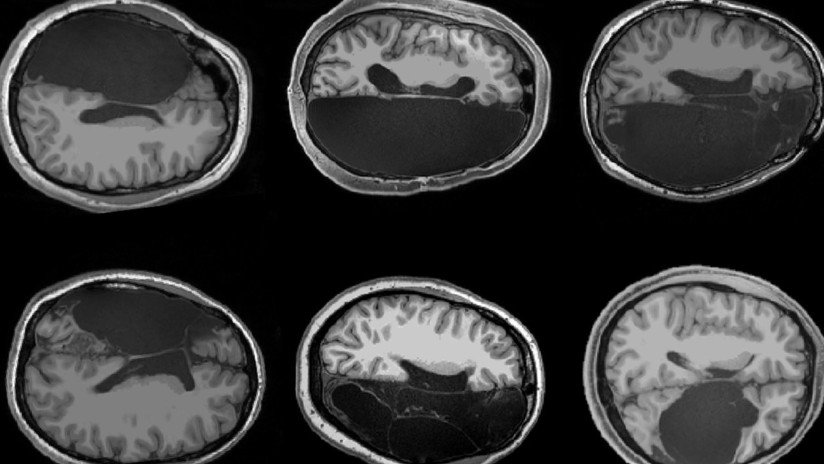

Tener una laringe baja proporciona más espacio para que la lengua se mueva, por lo que hasta ahora se pensaba que era un rasgo indispensable para producir ese tipo de sonidos. Sin embargo, el nuevo estudio señala que, además de que la laringe baja "no es exclusivamente humana", esta no es necesaria para emitir "patrones constantes en las vocalizaciones"

De hecho, se pensaba que los monos carecían del tipo correcto de laringe para generar una gama de sonidos, pero tras analizar su comportamiento y comunicación mediante gruñidos, los expertos han descubierto que estos animales son capaces de producir "vocalizaciones notablemente humanas".